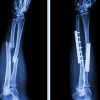

Selamat sore dokter, terkhusus dokter Spesialis Orthopedi

Mohon advisnya dokter

Jadi ada pasien mengeluhkan nyeri seperti tertusuk, tidak selalu, tapi sering, hilang timbul

Pasien post Orif ps H+113/6 bulan (tanggal 06 Agustus 2024)